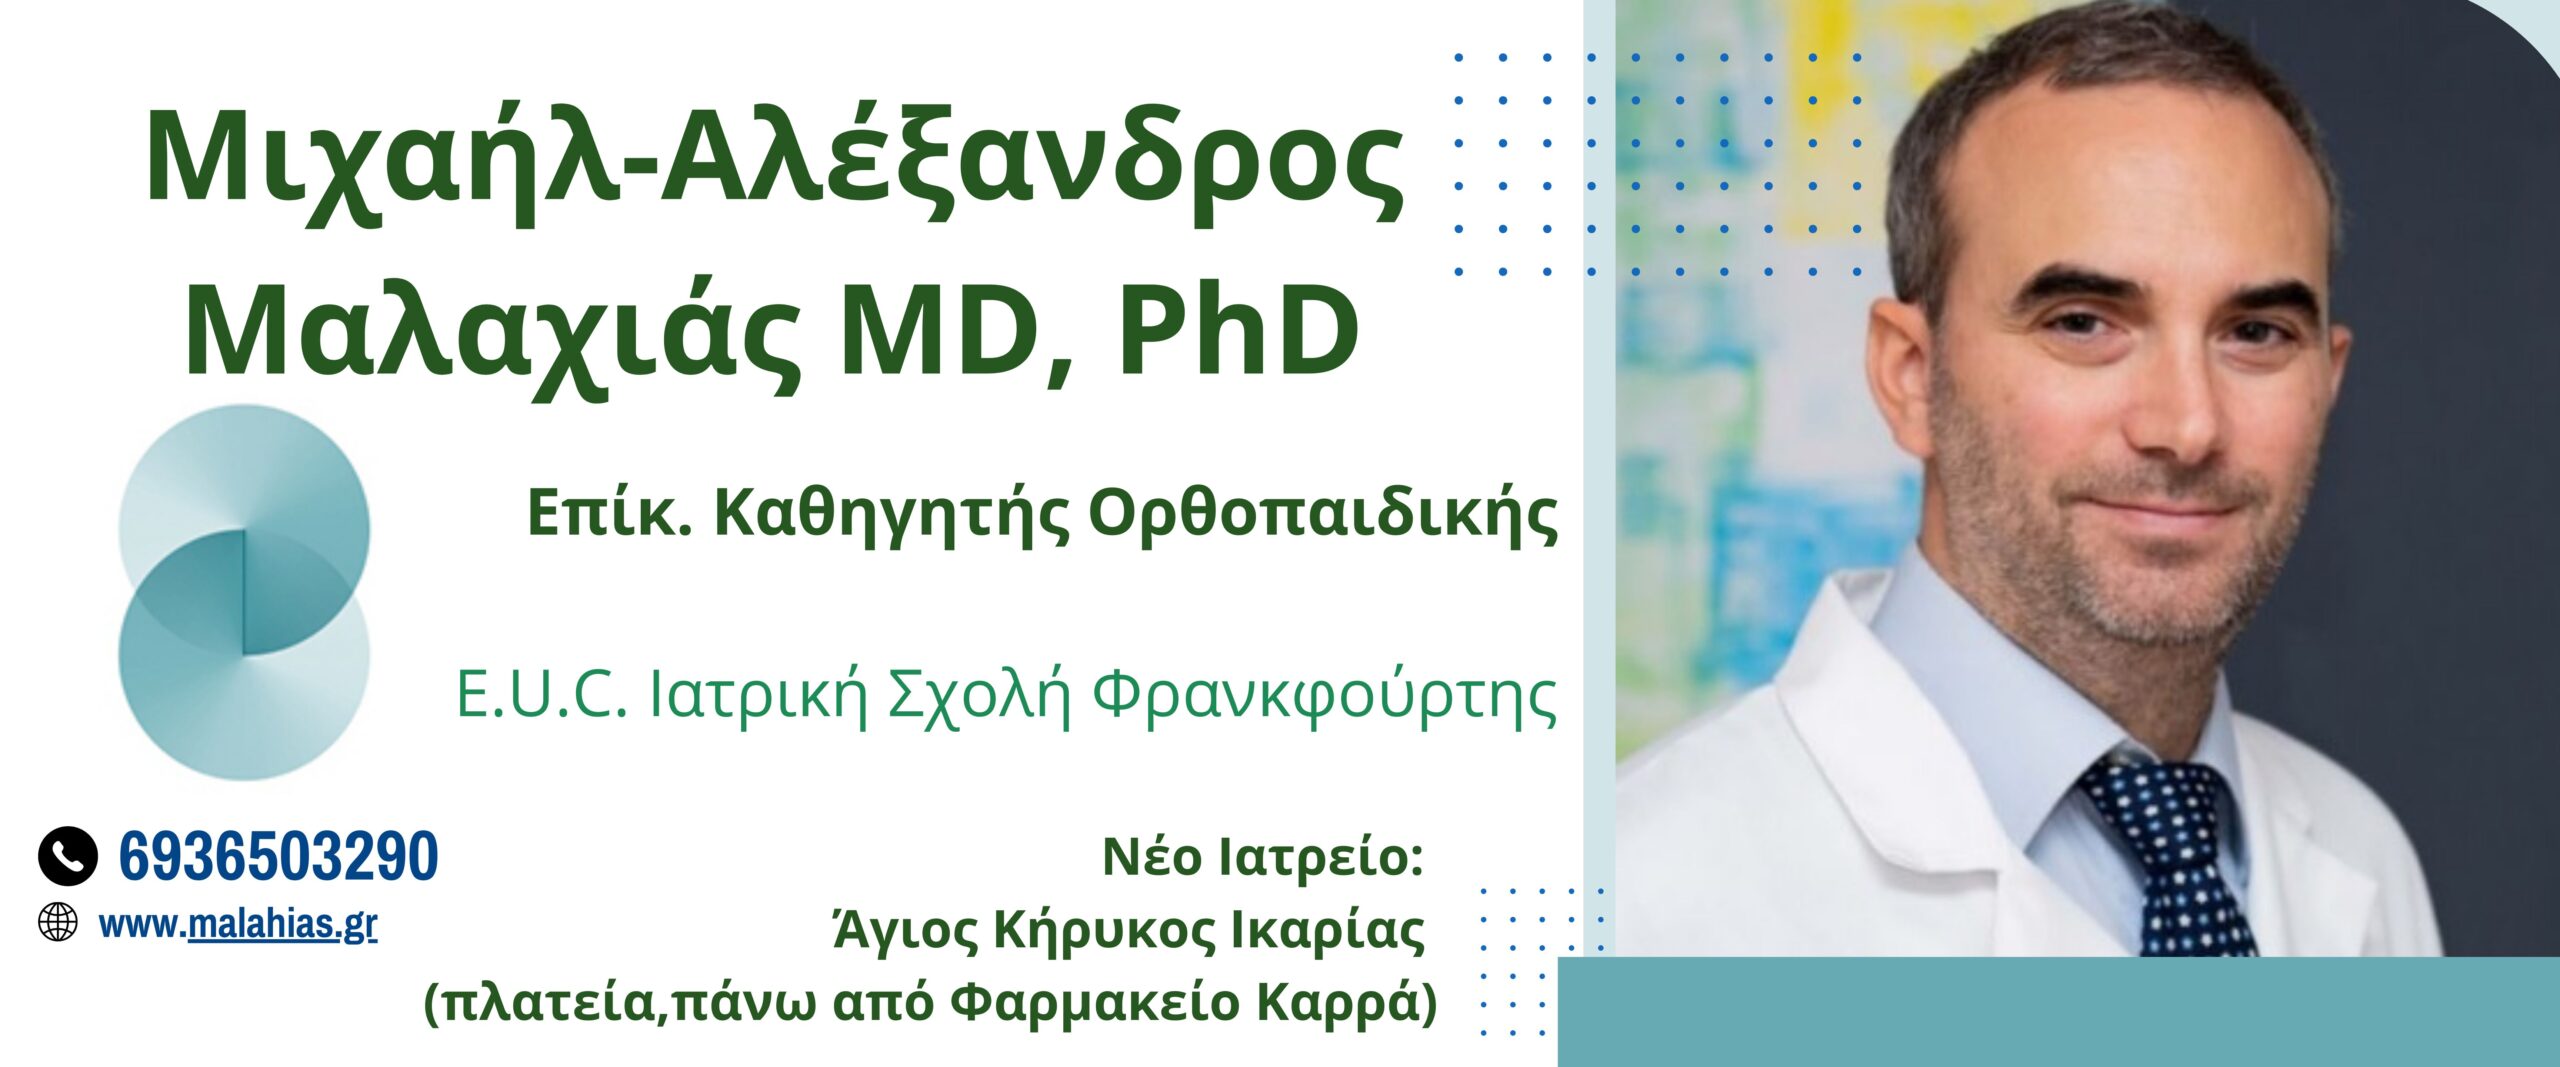

*Ο Δρ. Μαλαχιάς θα ταξιδέψει στην Ικαρία για να εξετάσει ορθοπαιδικούς ασθενείς με ραντεβού (τηλ.: 6936503290), στο ιατρείο του (πλατεία Αγίου Κήρυκου), την Πέμπτη 18 και Παρασκευή 19 Δεκεμβρίου.

Καλέστε 6936503290, για να κλείσετε ένα ραντεβού με τον Επίκ. Καθηγητή Ορθοπαιδικής, Δρ. Μιχαήλ-Αλέξανδρο Μαλαχιά.

website: www.malahias.gr